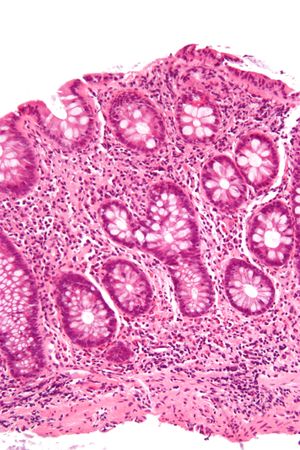

ميكروگراف يـُظهـِر cryptitis, a ارتباط مجهري لالتهاب القولون. H&E stain. | |